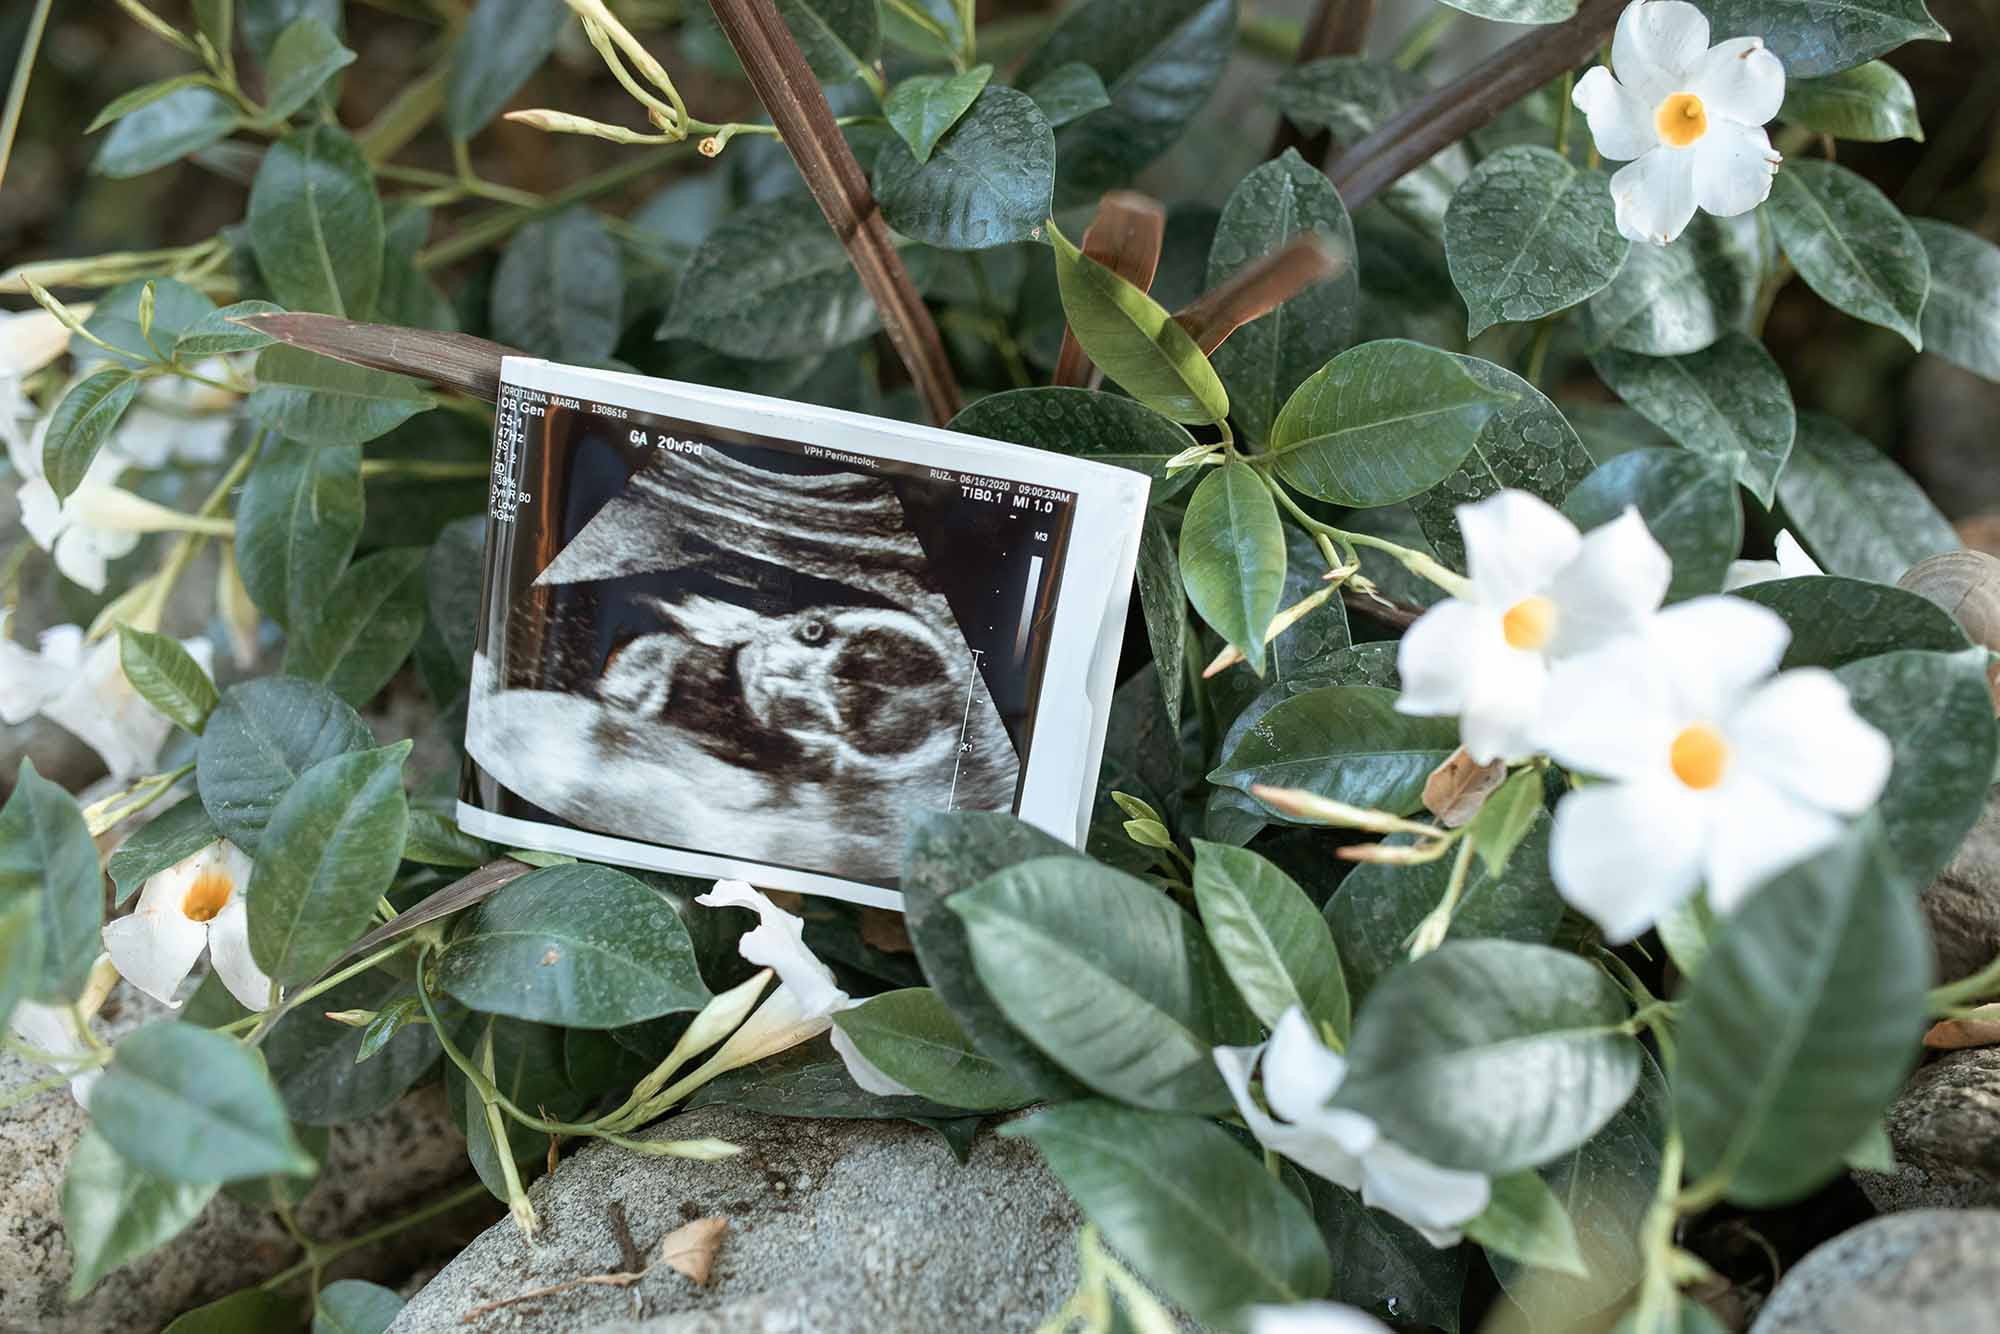

Viewing Your Baby’s First Images

Seeing your baby for the first time is unforgettable. The images reveal your baby’s shape and movements, offering a glimpse into their tiny world. This is often a highlight for new parents, capturing memories that last a lifetime. Take this opportunity to connect with your baby and celebrate their growth. You can even take home pictures to share with family and friends.